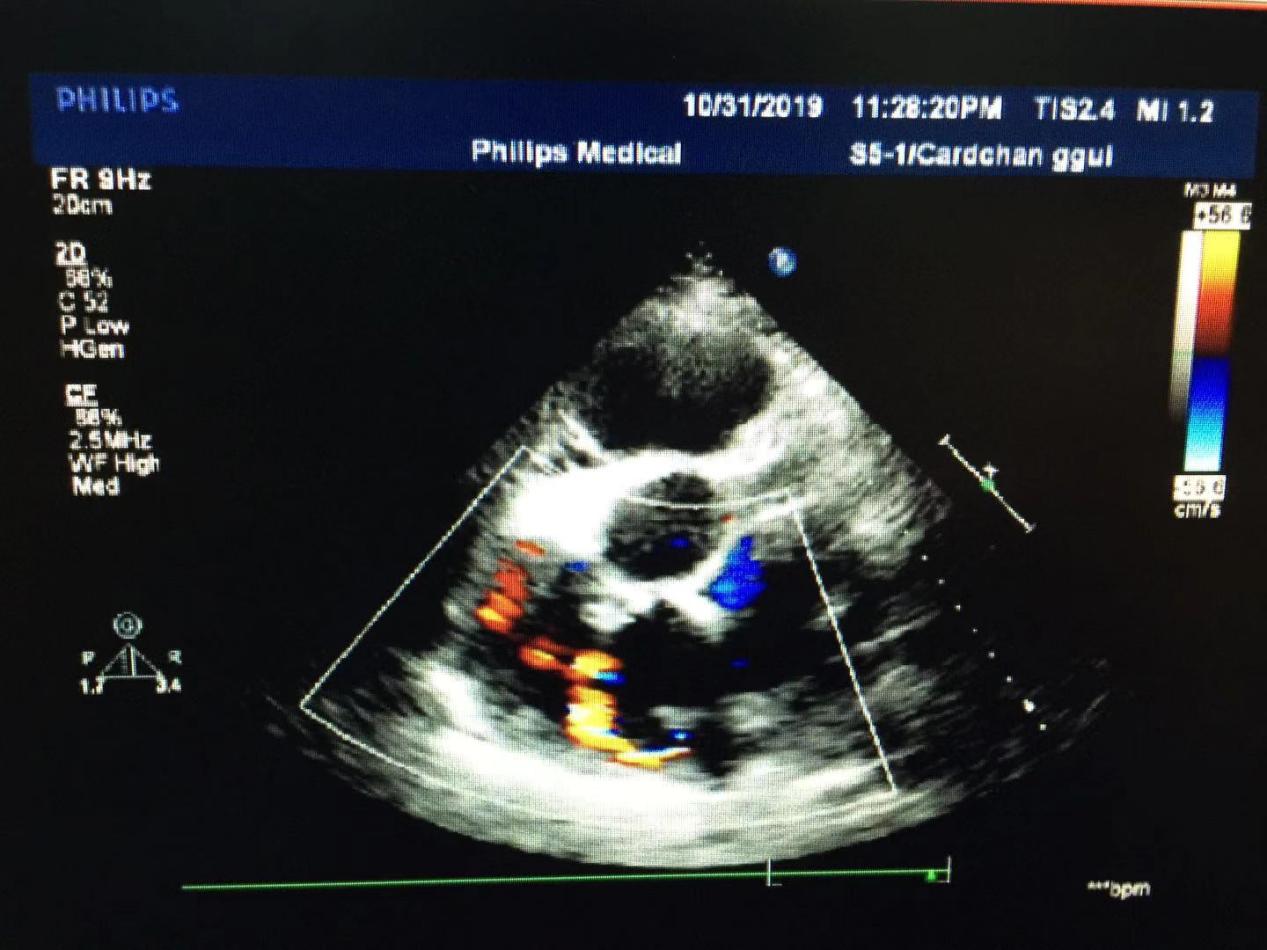

(右房内的冠状动脉瘘口)

超声所见:全心大,肺动脉主干内径增宽。左冠状动脉迂曲增宽,可视长度明显增加,开口处内径约14mm,增宽的左冠状动脉沿左房越过房间隔开口于右心房,瘘口直径约8mm。房、室间隔连续完整,左室侧后壁运动减弱,余室壁运动尚可。各瓣膜形态正常,二尖瓣、三尖瓣、主动脉瓣开启可,关闭欠佳。心包腔内探及液性暗区,左室后壁深约17mm,右室之前深约13mm。CDFI:于右房内可见以舒张期异常血流信号。二尖瓣、三尖瓣口可见收缩期返流信号。主动脉瓣口可见舒张期返流信号。

超声提示:1.左冠状动脉右房瘘;2.全心大;3.肺动脉高压(中度);4.二尖瓣中量返流;5.三尖瓣大量返流;6.左室收缩功能减低;7.心包积液(中量)。